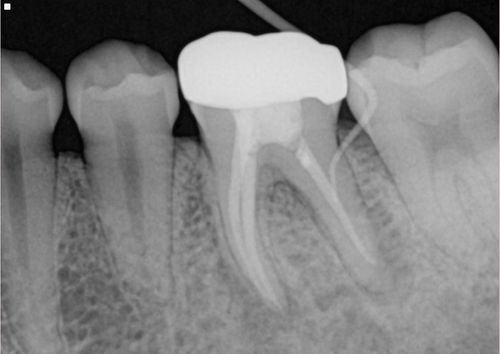

Retreatment